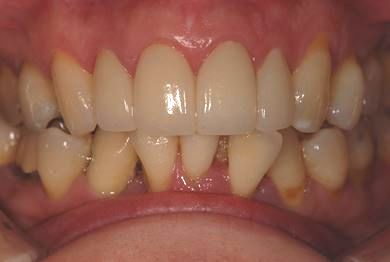

| 性別/年齢 | 女性 / 40歳 | ||||||||||||||||||||||||||||||||

| 主訴 | 前歯のつけ根の黒い部分を見えないようにしたい。 | ||||||||||||||||||||||||||||||||

| 治療方針 | 上顎前歯をセラミック治療にて審美的回復を行う。 | ||||||||||||||||||||||||||||||||

| 治療内容 | オールセラミッククラウン4本(セラミック用土台4本) | ||||||||||||||||||||||||||||||||

| 総治療費 | 573,300円 | ||||||||||||||||||||||||||||||||

| 治療期間 | 3ヶ月 |